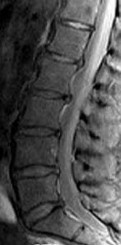

ORTHOPEDIC MCQS ONLINE 012 SPINE 1 Question 1A 56-year-old man has a chief complaint of leg weakness and inab…